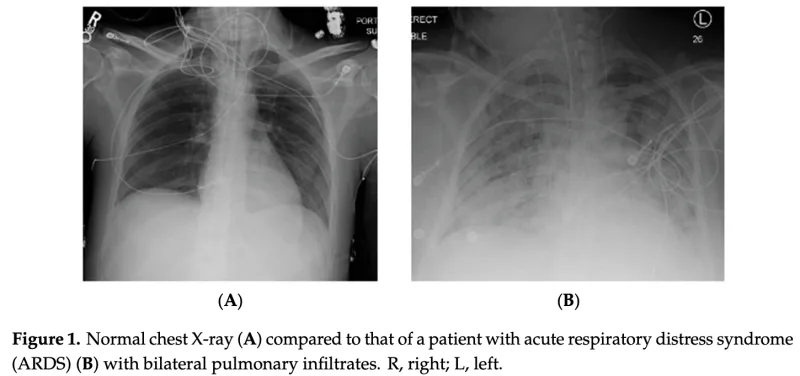

胸部X線写真を撮ったところ, 昨日より胸水は減っていましたが, 両肺が真っ白になっており, 急性呼吸促迫症候群(Acute Respiratory Distress Syndrome: ARDS)と診断.

急性呼吸促迫症候群と人工呼吸